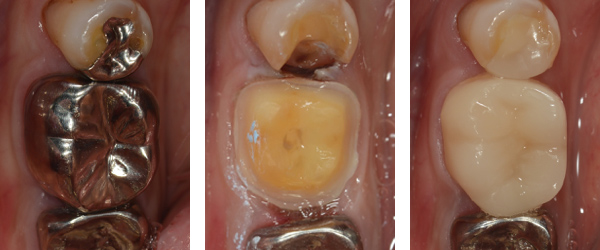

当院でのセレック治療の症例

30代女性。下の奥歯の違和感と笑ったときに銀歯が目立つ事が気になっていた。

銀歯を外したところ。手前の歯は詰め物の下が虫歯になっていた。

虫歯を取りきり、セレックで削りだしたセラミックの被せ物、詰め物をセットした。